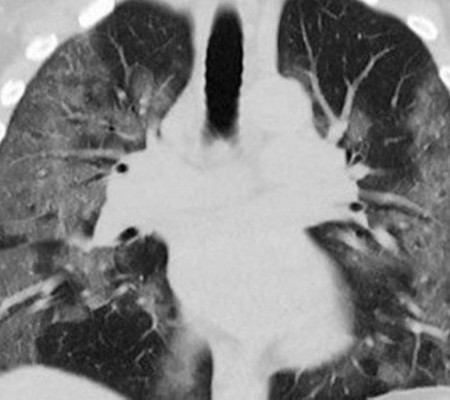

Três dias após a operação, entretanto, a receptora apresentou febre, a pressão arterial caiu e a respiração se tornou difícil. Exames de imagem mostraram sinais de infecção pulmonar.

À medida que sua condição piorava, a paciente desenvolveu choque séptico e problemas na função cardíaca, levando a paciente à morte. Os médicos decidiram fazer o teste de SARS-CoV-2, disse Kaul. As amostras dos seus novos pulmões deram positivo.